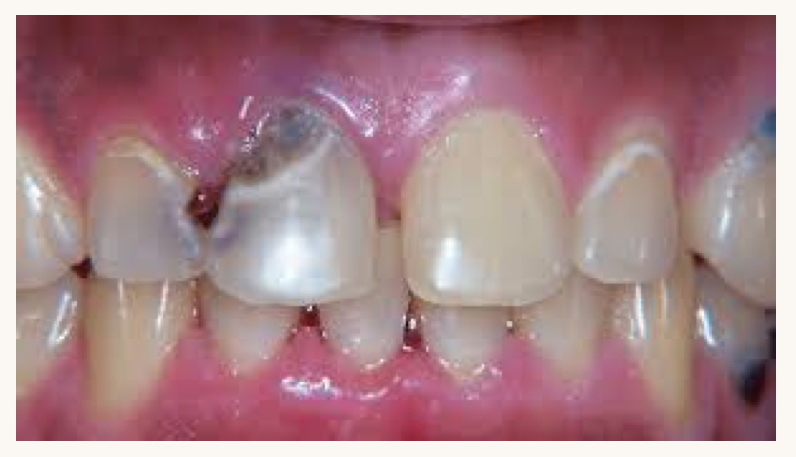

what is this condition and what mineral is this person likely deficient in?

pale/swollen tongue, angular cheilitis

iron deficiency

what dietary factors are correlated with oral candidosis?

deficiencies in iron, B1, B2, B9, vitamin C, K, and zinc

also excess carbohydrates

what nutrient deficiencies are related with these oral lesions?

deficiencies in B9, B12, vitamin C, A